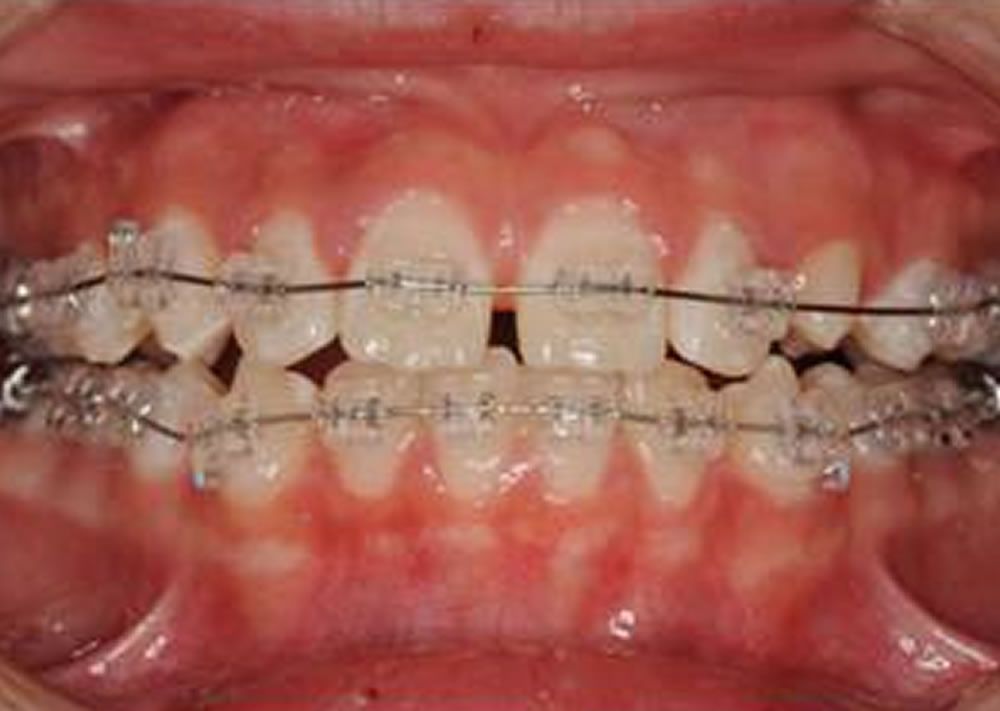

BiVi歯科・矯正歯科で実施した小児矯正の治療例をご紹介

▼当院で実際に行った小児矯正治療の症例をご紹介します。